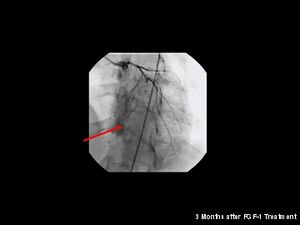

حدد الباحثون بمتشفى كليفلند (Cleveland Clinic) في دراسة تمت سنة 2006،منطقة في كروموسوم 17 مختصة بالعائلات التي تصاب بعدة حالات من الجلطة القلبية(myocardial infarction). كما يوجد خلاف حول العلاقة بين الإصابة بمرض تصلب الأوعية الدموية (atherosclerosis) والعدوى بالبكتيريا Chlamydophila pneumoniae،بينما أُثبت وجود هذه البكتيريا الذي تعيش داخل الخلية في صفيحة الكولسترول لدى المرضى المصابين بتصلب الأوعية، فما زالت هذه البراهين غير حاسمة فيما إن كانت هذه البكتيريا بحد ذاتها عامل مسبب للمرض. لم يظهر العلاج بالمضادات الحيوية (antibiotics) لمرضى تصلب الأوعية الدموية أي تقليل لخطر الإصابة بالنوبة القلبية (heart attacks) أو أمراض الأوعية التاجية الأخرى. منذ سنة 1990 والبحث جاري نحو خيارات جديدة للعلاج لأمراض أوعية القلب التاجية تُركز على استخدام ما يسمى تكوّن الأوعية الدمويةangiogenesis والخلايا الجذعية stem cell. حيث أجريت الكثير من التجارب السريرية إما بتطبيق العلاج ببروتين عامل النمو لتكوّن الأوعية الدموية (angiogenic growth factor) مثل: FGF-1 أو VEGF ،أو العلاج بالخلايا باستخدام أنواع مختلفة من الخلايا الجذعية. وما زالت الأبحاث قائمة توعد بمستقبل مشرق للعلاج خصوصا فيما يتعلق ب FGF-1 والانتفاع الخلايا المُولدّة للخلايا المبطّنة للأوعية الدموية endothelial) progenitor cells).